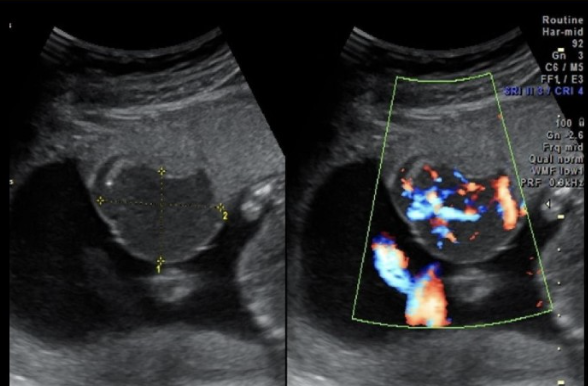

what congenital anomaly is shown

a) renal agenesis

b) duodenal atresia

c) anal atresia

d) posterior urethral valves